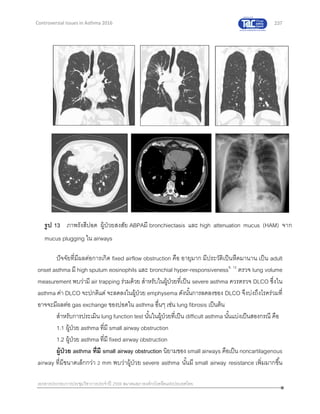

in Asthma 2016